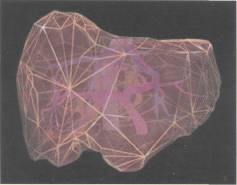

Tüm damar yapılarını da içeren üç boyutlu kalın bir karaciğer oluşturma fikri 5-6 yıl öncesine kadar yalnızca bir hayal olarak kabul ediliyordu. Dr. Vacanti'nin 1997 yılında bir farenin sırtında insan kulağı geliştirdiği günden beri, üç boyutlu ve damarlı yapay karaciğer fikri hayal olmaktan çıktı. Harvard Üniversitesi'ndeki bilim

adamları orijinal karaciğer benzeri bir model oluşturdular. Yapay karaciğer yaratmada en önemli basamak, karmaşık damar yapısını oluşturmak. Bu nedenle ilk olarak, vücuttan çıkartılmış bir karaciğerin damarlarının içine, özel bir sıvı plastik materyal enjekte ediliyor. Bu sıvı kısa süre içinde katılaşarak damarların şeklini alıyor. Daha sonra karaciğer dokusu özel sıvılarla eritilerek yok ediliyor. Geriye yalnızca katılaşmış ve damar şeklini almış olan madde kalıyor. Kurumuş ağaç dallarına benzeyen bu yapı, karaciğerin damar yapısını temsil ediyor. Bu yapının görüntüleri bilgisayara aktarılarak üç boyutlu görüntüler elde ediliyor. Bu görüntüler yardımıyla silikon kalıplar hazırlanıyor. Silikon kalıpların içine polilaktik glikolik asit (PLGA) yapısındaki bir madde dökülüyor. Böylece karaciğer

damarlarının organik bir iskeleti oluşturuluyor. Bu iskeleti oluşturduktan sonraki aşamaysa hücrelerin oluşturulması. Damar iskeleti çevresine yerleştirilen karaciğer hücreleri, belirli büyüme faktörleri yardımıyla çoğalarak organın kalın etli kısmını oluşturuyorlar. Bir sonraki aşamaysa damarın oluşturulması. Bunun için süngerimsi yapıda olan PLGA içine damar hücreleri enjekte ediliyor. İskelet, hücrelerin çoğalması için gerekli büyüme faktörlerini ve besin maddelerini içeriyor. Damar hücreleri iskelet boyunca ilerleyerek karaciğer hücrelerine yapışıyor. Burada çoğalan damar hücreleri, iskelet çevresinde birleşerek tam bir damar yapısı oluşturuyorlar. PLGA iskelet birkaç ay içinde kendiliğinden eriyerek geride karaciğer hücreleri ve içinde damarları olan yapay bir organ bırakıyor. Bu şekilde oluşturulan yapay karaciğer hayvanlarda denendi. Oldukça iyi kan akımının sağlandığı bu organlarda dışarı kan sızıntısı da gözlenmedi.